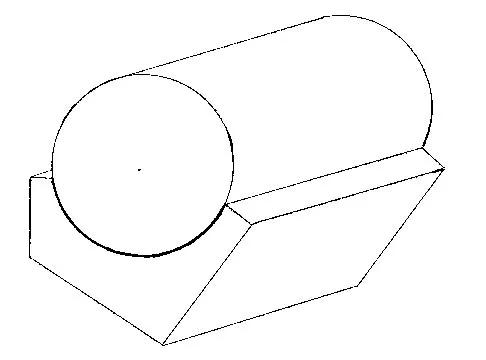

Consider the theoretic articulation shown in Figure 11 as femoral and tibial components of a total knee prosthesis in which the components fit like a "roller in trough." Which of the following best describes the articulation?